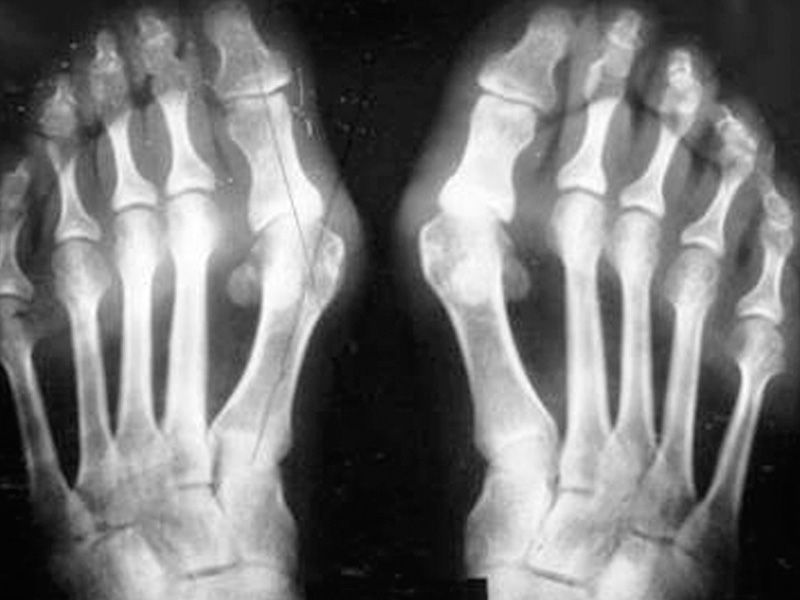

При возникшей боли стоит обратиться в поликлинику за медицинской помощью к ортопеду, ревматологу. Доктор осматривает пациента, проводит опрос, выслушивает жалобы. Осмотр стопы заключается в оценке и анализировании деформации сочленения, подвижности и степени боли. Диагностировать артрит стопы не затруднительно.

Основными способами диагностики суставов являются УЗИ, МРТ, КТ. Чтобы выяснить настоящую и точную причину артрита проводят общий анализ крови. Для определения состояния синовиальной жидкости совершают пункцию сочленений.